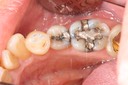

Alan Tamashiro #18 pre-op

Alan Tamashiro #18 caries removal

Alan Tamashiro #18 prep

Alan Tamashiro #18 finish